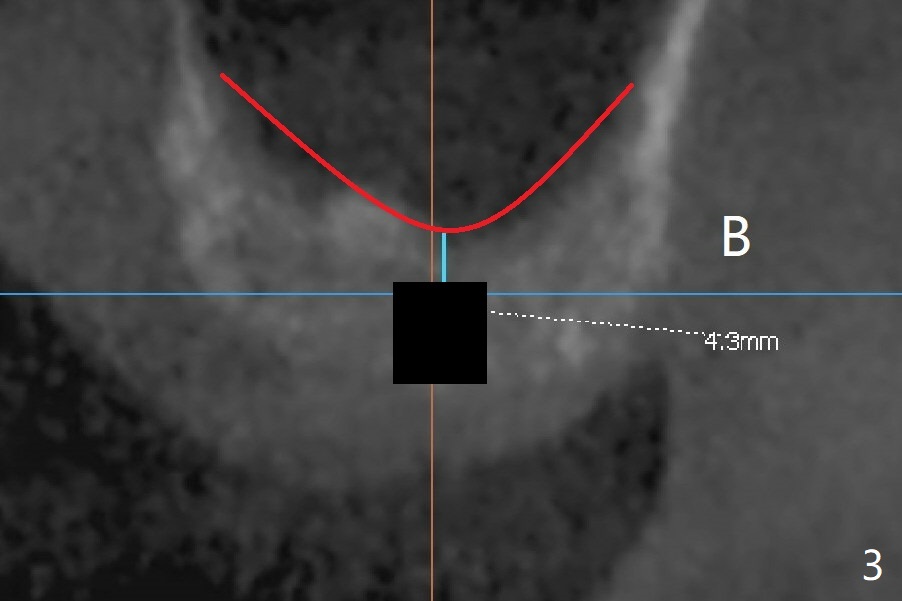

A 48-year-old man returns for CT 4.5 months post infected implant removal with bone graft at #15. The bone height reduces from 6-10 mm to ~ 4 mm (Fig.1). To place a 5x7.3 mm implant (Fig.2), initial osteotomy for ~3 mm in depth and in diameter will be aided by guided surgery (Fig.3 (red line: sinus membrane)). Internal sinus lift is going to be conducted with Magic Lifter free hand or in the middle of the tube (Fig.4 arrows). The specially designed lifter is able to lift the sinus floor without tearing the membrane. To prevent and repair membrane injury, one or 2 pieces of PRF membrane will be inserted underneath the lifted structures (Fig.5 yellow), followed by bone graft (green circles). Then 3.5-4.5 mm taps will be used with guide to further expand and condense the osteotomy. With more graft to be placed, the 5x7.3 mm implant will be placed (Fig.6 pink).